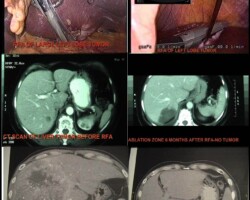

Resection of large retroperitoneal sarcoma including right and transverse colectomy and right hepatectomy